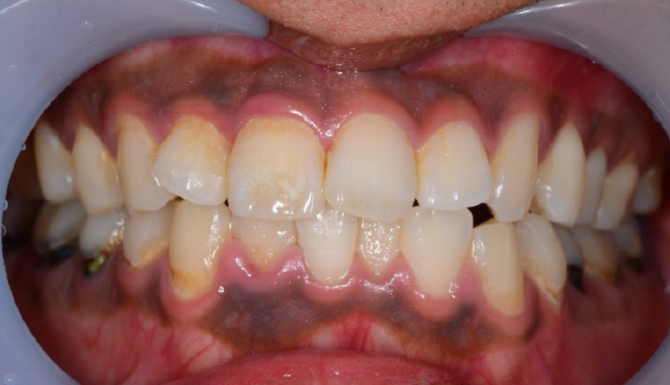

CASE2

Before

After

年齢・

性別

20代・男性

主訴 歯ぐきの色が気になる

治療

回数

1回

費用

ガムピーリング 上下顎

11,000円×1

(2025年9月現在)

内容

ガムピーリング

リスク・

副作用

・ヒリヒリとした痛み

・フェノール、アルコール類にアレルギーは禁忌

・施術後1〜3日くらいは歯ぐきが白っぽくなる